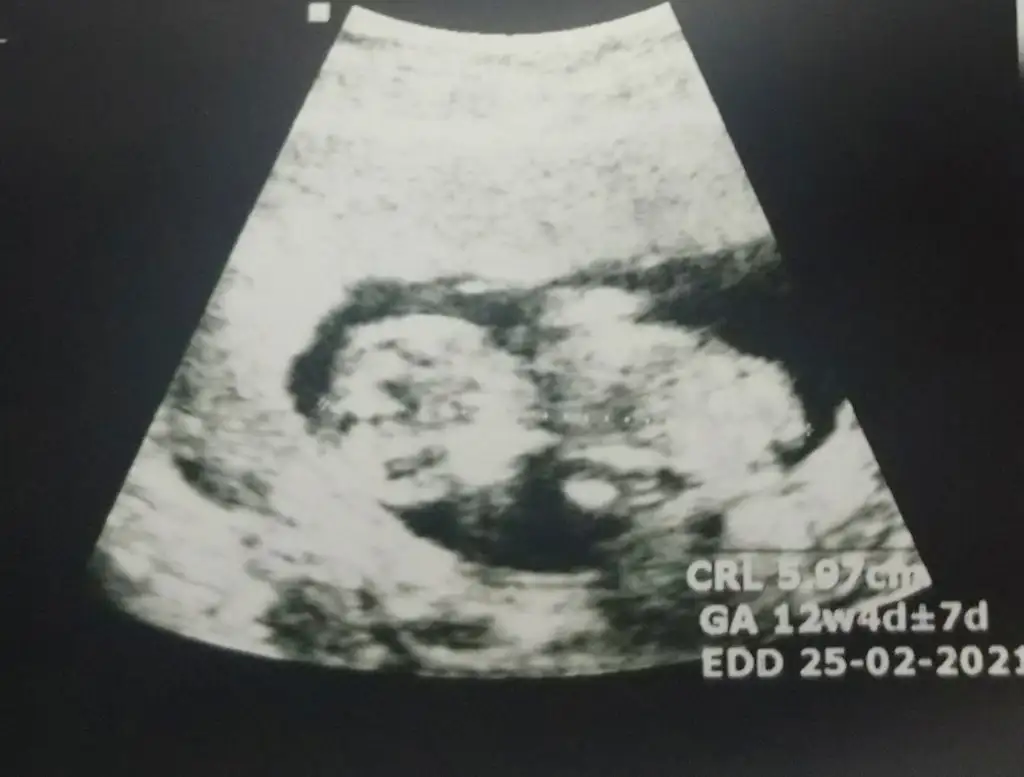

Merhaba benim bebegime de bi tahmin yapar misiniz siz ve anlayan diger arkadaşlar 😊

Mümkünse anlayanlardan birer tahmin alabilirmiyim? Çok teşekkürler şimdiden :KK54: